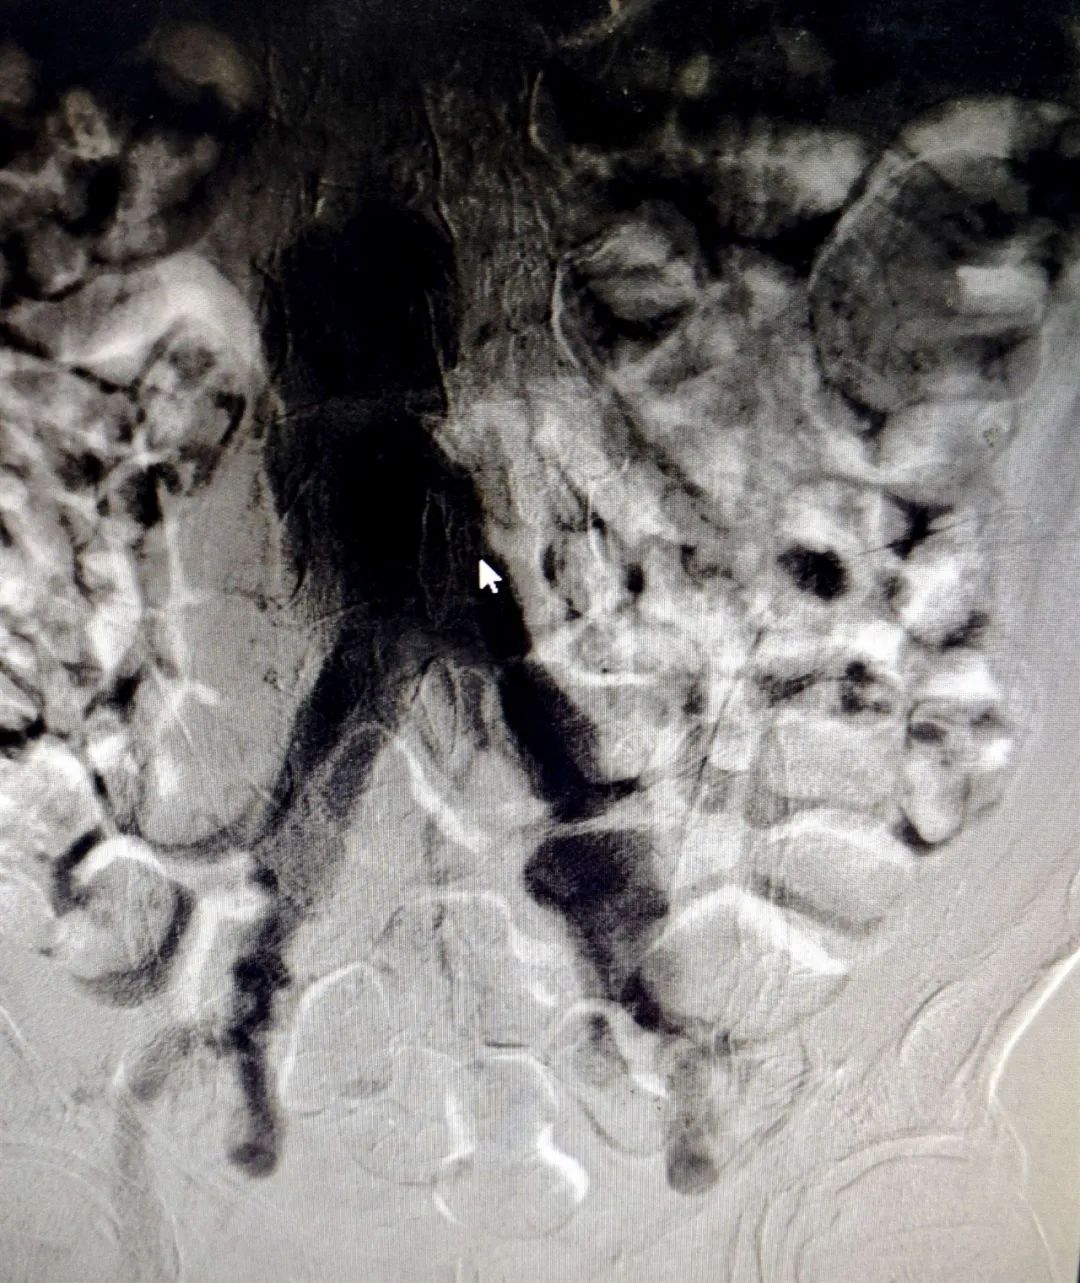

支架植入前造影